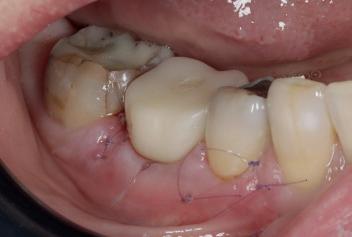

Marketing and branding yourself using social media platforms is essential as a selfemployed individual. Breaking that fear and anxiety of showcasing and promoting your before-and-after work, and highlighting patient testimonials on social media is not only important to demonstrate your skillset as a young dentist but also to boost your reputation and recognition for welcoming new patients. Having been fortunately selected as a finalist for multiple awards in the past including this year’s Dental Awards, it has not only boosted my esteem and confidence as a young dentist, but has encouraged me to keep steering this journey forward for the benefit of my patients’ healthcare and my own ability to provide excellent dentistry. Plus, receiving a shiny plaque to put on the wall for patients to see provides a confidence boost for them, as well as myself.

I personally use Instagram for my content. I was always hesitant to post images of my work in fear of being judged by other dentists, but eventually overcame this and told myself to have confidence in the quality of my work and just do it. That mindset has worked in my favour since. Sharing before-and-after cases (with patient consent), posting educational videos about common procedures, and fun moments behind the scenes to make your practice feel welcoming speaks for itself. Be sure to engage with your audience by answering questions, responding to comments and showing that you care.